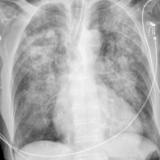

APE 3

Date: 11/05/2005

Views: 3886

APE 4

Views: 2825